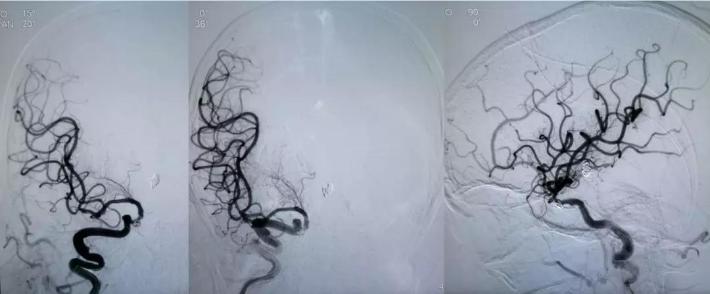

DSA

右侧颈内动脉虹吸段夹层动脉瘤,右侧大脑前动脉A1段纤细

拟通过微导丝将支架微导管预置到右侧大脑后动脉,但微导丝支撑力不足,直接通过基底动脉至右侧大脑后动脉较困难,先在动脉瘤腔内部分填塞弹簧圈(4mm*10cm),以作支撑,再将微导丝带微导管置入右侧大脑后动脉,经微导管送入LEO支架(2.5*18mm)

采用支架半释放技术,LEO 2.5*18mm半释放,继续送入编框圈编框成篮,再依次填入填充圈

采用支架推挤技术,推挤支架,保护双侧大脑后动脉、右侧小脑上动脉,继续将动脉瘤填塞致密,完全打开支架

处理右侧颈内动脉虹吸段夹层动脉瘤。

预置入支架导管,栓塞动脉瘤用微导管头端超选进入动脉瘤腔,通过支架导管送入Enterprise支架(4.5*22mm)并打开支架,填入弹簧圈栓塞夹层动脉瘤。但此时发现大脑前动脉A1段不显影。

治疗后

对侧造影评估,前交通开放,左侧大脑前动脉经开放良好的前交通动脉向右侧大脑前动脉A2段各分支血管供血良好,结束手术